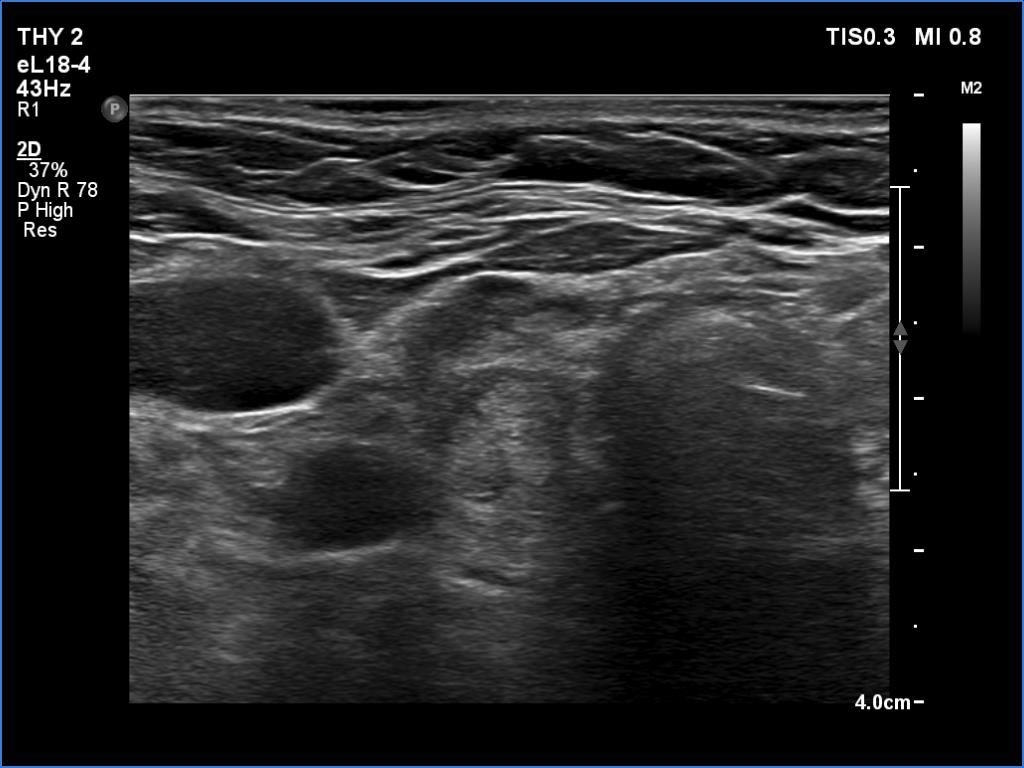

Ultrasonography: The right lobe had several discrete hypoechoic areas within an echonormal background. The left lobe had a larger hypoechoic area resembling the presentation of central hypoechoic area-type form.

Comment: The central hypoechoic area-type presentation is always bilateral. The pattern in this case should be regarded as focal form of lymphocytic thyroiditis.